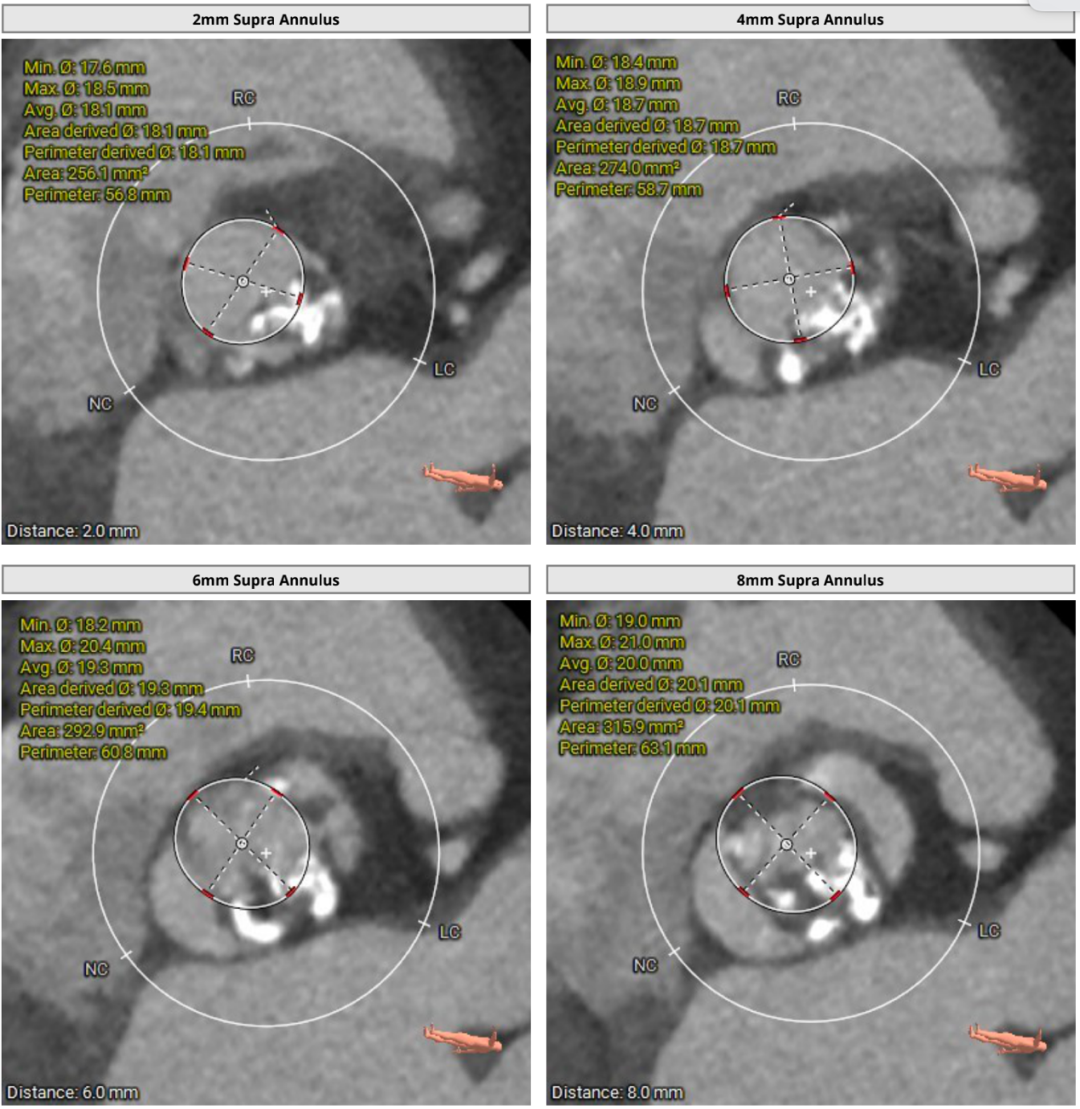

瓣上结构测量

随着TAVR技术在国内的普及,主动脉瓣狭窄患者有了更多的治疗选择。本例患者为主动脉瓣重度狭窄伴轻度反流,患者伴代偿性心力衰竭,术前评估适宜行TAVR手术,有TAVR手术指征。术前CT分析提示患者为Type0型二叶式主动脉瓣,瓣环径23.5mm,瓣叶增厚伴重度钙化,钙化主要分布于无窦与左窦交合缘及瓣叶边缘,LVOT呈类直筒状形态,预估人工瓣膜会有较明显形变,有根部撕裂、损伤风险。左室流出道可提供辅助锚定,综合预估瓣膜锚定定位精度要求较高。患者又为横位心,主动脉弓距及夹角尚可,升主动脉扩张,需警惕血管夹层、破裂等风险,对经导管主动脉瓣输送系统过弓、跨瓣的性能要求较高。综合以上因素,该患者行TAVR手术对术者快速、精准的操作能力及手术团队的密切配合要求较高。广东省人民医院赣州医院(赣州市立医院)倪忠涵院长带领团队,经过心内科、心外科、麻醉科、超声等多学科团队的缜密讨论,最终决定为患者施行TAVR手术治疗。